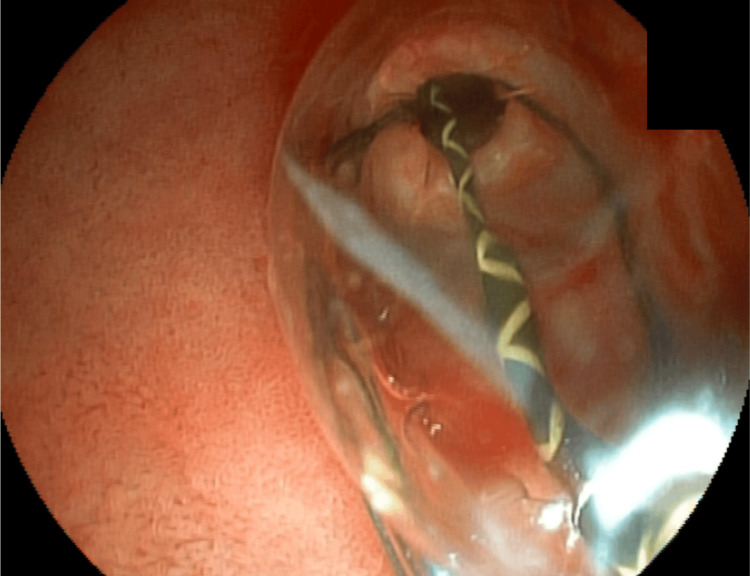

The endoscopist then recommended a later endoscopic approach, removing the basket, stone, and prosthesis. However, the surgeon of the case opted for open surgery two days later and cholecystectomy, removal of the prosthesis, stone, and basket by duodenotomy, and CBD opening (Figure 11).

There were three possible approaches to resolve this case. The ideal strategy would have been delayed cholangioscopy with laser lithotripsy, followed by removal of the basket, stone, and stent. Alternatively, the case could have been managed laparoscopically through cholecystectomy, choledocholithotomy, and extraction of the basket, stone, and stent. However, definitive treatment was achieved via laparotomy, with cholecystectomy, choledocholithotomy, and removal of the basket, stone, and stent.